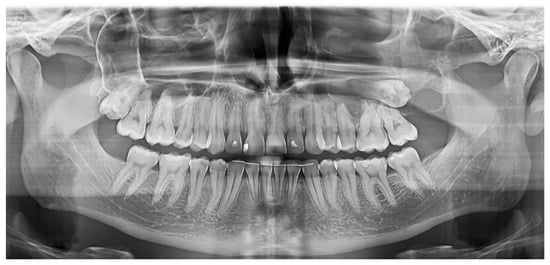

2.2.2. Case 2